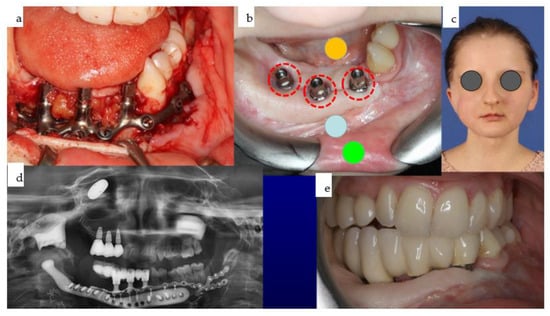

Figure 30. (ae): Different views of the IPS Implants® Preprosthetic during (a) and three months after (b) insertion are presented; the red dotted circles around the posts reveal healthy tissues (b). The yellow (floor of the mouth), light blue (vestibule), and green (inner lining of the lip) spots demonstrate the successful subunit separation due to the additional microvascular radial forearm flap, which was placed ahead of bimaxillary dental rehabilitation. The clinical appearance is depicted in (c); the orthopantomogram summarizes all biomaterials and implants placed into the patient over many years, including the gold weight implant for the right upper eyelid, patient-specific PEEK implant (non-radio-opaque) for the right temporal fossa (only fixation screws are visible), right total joint replacement, IPS Implants® Preprosthetic with mounted final superstructure, and the conventional three bone-level tapered dental implants with crowns in the right maxilla (d). An intraoral view matching the clinical picture (c) is shown in (e) with the dental arches in occlusion. Mild right mandibular sagging led to occlusal correction over time.